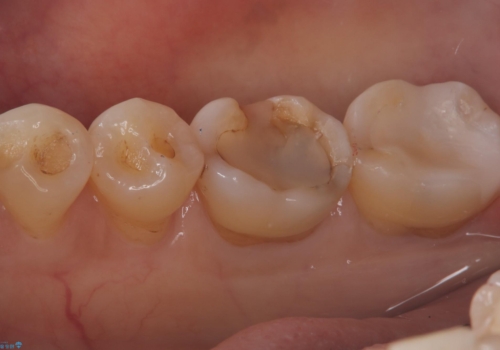

- 主訴:プラスチックの劣化が気になる。

咬合面にCR(コンポジットレジン)修復が広範囲にされており、劣化のしにくさや審美性からセラミックインレーでのやり替えとなりました。

今回残存歯質量から破折のリスクを説明し、クラウンでのやり替えも提案しましたが歯質切削量が多くなることから一度インレーで様子を見ることとなりました。